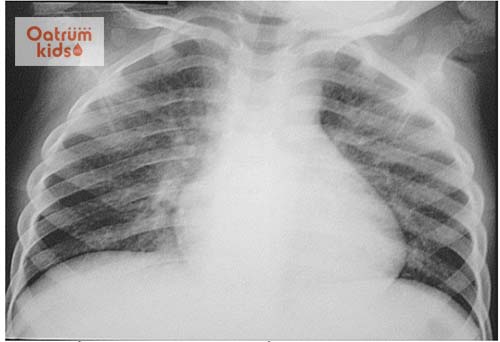

Bệnh sởi có thể gây một số biến chứng về đường hô hấp như bệnh viêm thanh quản, viêm phế quản, viêm phế quản-phổi. Những bệnh này thường do bội nhiễm. Khi bị mắc bệnh viêm phế quản – phổi bệnh nhi có thể tử vong nếu không được điều trị kịp thời và đúng phác đồ.

Nếu không được điều trị kịp thời trẻ dễ bị biến chứng đường hô hấp